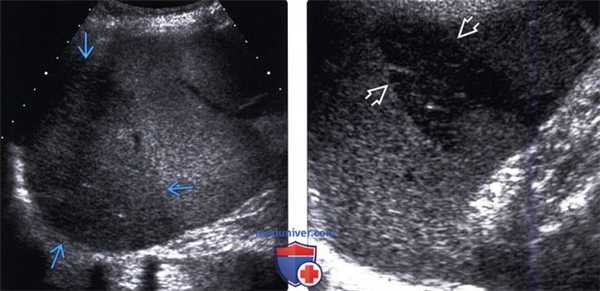

(Левый) При УЗИ в черно-белом режиме видна округлая зона полярного инфаркта селезенки. Гипоэхогенная зона инфаркта имеет четкие края. При цветовой допплерографии (не показана) в зоне инфаркта отмечается отсутствие кровотока.

(Правый) Показан разрыв селезенки, симулирующий инфаркт: четко отграниченная гипоэхогенная лентовидная зона, тянущаяся в субкапсулярную область. При дифференциальной диагностике важнейшее значение имеет факт травмы в анамнезе. У пациентов с тупой травмой живота из интраперитонеальных органов наиболее часто повреждается именно селезенка.